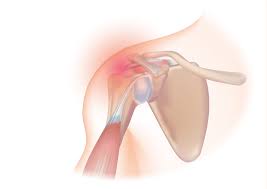

회전근개파열이란?

회전근개는 어깨뼈와 위팔뼈를 연결하는 네 개의 힘줄(극상근, 극하근, 소원근, 견갑하근)로 이루어진 구조입니다. 이 힘줄들이 반복적인 사용, 외상, 노화 등으로 손상되면 ‘회전근개파열’이라 부릅니다.

어깨가 찢어지는 듯이 아프거나, 팔을 들 때마다 뻣뻣한 느낌이 드는 적 있나요? 단순한 근육통이라 생각하고 방치하기 쉽지만, 이런 통증은 회전근개파열일 가능성이 높습니다. 회전근개는 어깨를 감싸는 4개의 힘줄로, 우리가 팔을 들거나 회전할 때 중요한 역할을 합니다. 이 부위에 손상이 생기면 팔을 제대로 움직이기 어렵고, 일상생활에도 큰 영향을 미칩니다.